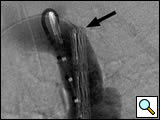

The modified original delivery sheath is then inserted snuggly into the hub of the long 16- or 18-French sheath over the guidewire. The endograft is transferred into the new sheath by advancing the delivery catheter while ensuring that the end of the original sheath is tightly nested in the receiving sheath. The original delivery system is then removed over the guidewire. The blunt back end of the dilator from the new sheath is inserted over the guidewire and used to push the endograft to the end of the long delivery sheath. The 5-French pigtail catheter is re-advanced into the distal aortic arch and control angiograms are obtained through the 5-French pigtail catheter prior to deployment of the endograft (Figure 3A). The endograft is deployed by withdrawing the sheath while maintaining the endograft in a fixed position with the pusher catheter. Angiograms are obtained through the 5 French pigtail catheter before and after gentle inflation of appropriate sized angioplasty balloons within the endografts (Figure 3B).

Figure 3a: Pre- and post-deployment digital subtraction angiograms (DSA) of transected aorta. Pre-deployment DSA with a 22-mm diameter stentgraft advanced to the end of the 18-French sheath (black arrow) using the back end of the sheath dilator as a pusher (white arrow). The endograft was repositioned prior to deployment.